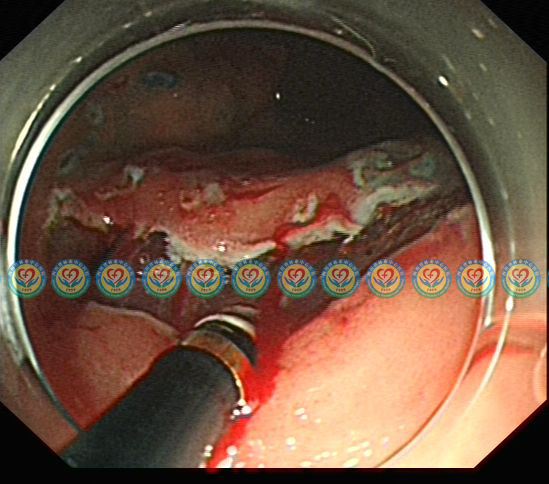

显露粘膜下血管,逐一处理

沿固有肌层表面剥离病变